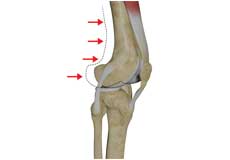

Osteoarthritis also called degenerative joint disease, is the most common form of arthritis. It occurs most often in older people. This disease affects the tissue covering the ends of bones in a joint (cartilage).In a person with osteoarthritis, the cartilage becomes damaged and worn out causing pain, swelling, stiffness and restricted movement in the affected joint.

High Tibial Osteotomy

High tibial osteotomy is a surgical procedure performed to relieve pressure on the damaged site of an arthritic knee joint. It is usually performed in arthritic conditions affecting only one side of your knee and the aim is to take pressure off the damaged area and shift it to the other side of your knee with healthy cartilage.